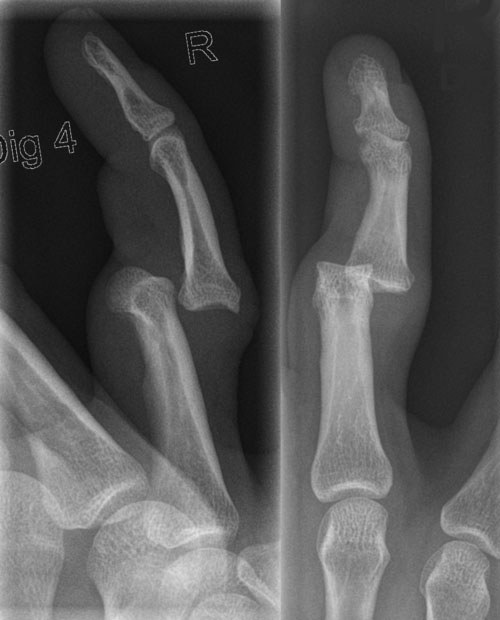

PIP dislocation usually happens dorsally from longitudinal compression and hyperextension, such as being hit by a ball at the fingertips, and, thus, dislocation is most likely to happen at the middle finger.11 (See Figure 2.) Volar dislocation is infrequent and has a higher complication rate, with a lower success rate of reduction.12,13 In cases of volar dislocation, the central slip may be ruptured. If left untreated, this can result in a pseudo-boutonnière deformity, characterized by persistent PIP joint flexion with loss of DIP extension.14

Figure 2. Finger Dislocation of Proximal Interphalangeal Joint |

![]() |

Source: Hellerhoff. https://commons.wikimedia.org/wiki/File:Finger_luxation_D4_PIP.png |